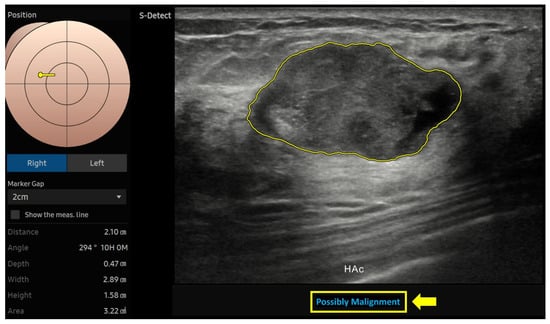

2.4. AI Analysis

| HAc | 81.4 (70.3–89.7) p < 0.001 *** | 87.9 (82.4–92.2) p < 0.001 *** | 86.2 (81.4–90.1) p < 0.001 *** | 71.3 (62.4–78.7) p < 0.001 *** | 92.8 (88.7–95.5) p < 0.001 *** | 0.760 (0.677–0.832) |